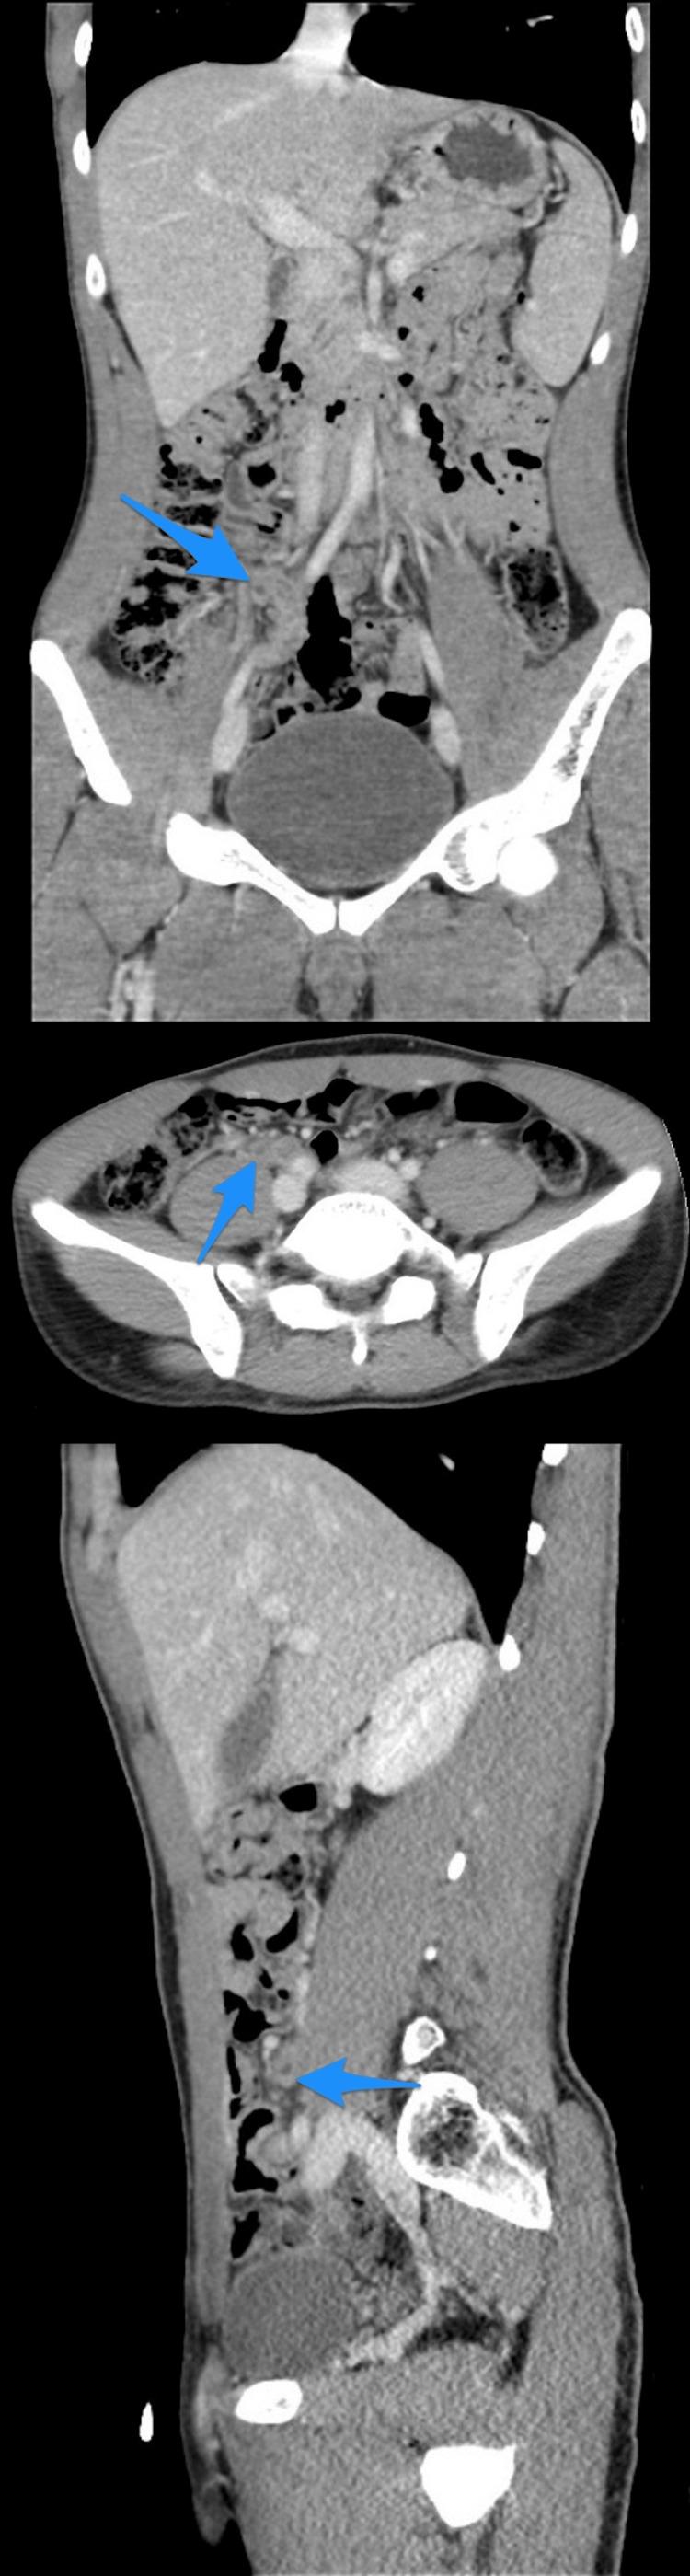

Appendicular diverticulitis (AD) is a rare entity characterized by the inflammation of the arising diverticulum of the appendix. It has been reported to carry a high risk of perioperative complications, such as bleeding and perforation. Furthermore, multiple articles have highlighted the importance of diagnosing AD early due to its strong association with malignancies. Limited published cases concerning AD in our country and globally are available in the literature. Hence, we present in this article a case series of five exciting cases of incidental findings of AD that were initially diagnosed as acute appendicitis based on clinical evaluation and imaging findings. In our series, we performed a retrograde evaluation of the computed tomography scans of all five cases that showed diverticula. In conclusion, histopathological evaluation remains the method of choice to reach the definitive diagnosis; however, it is essential to highlight the relevance of imaging in diagnosing AD preoperatively in the early stages to reduce morbidity and mortality.